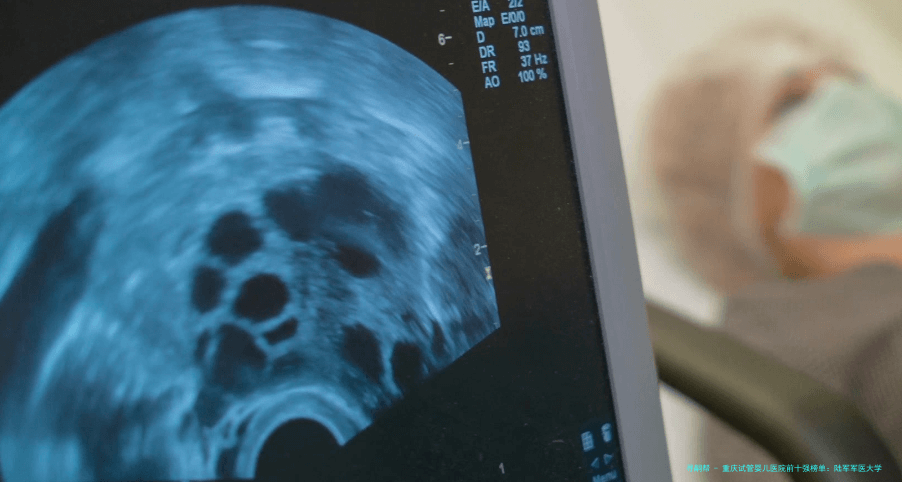

女性的生育本领跟着年纪增长而减少,尤其是35岁未来,卵巢储备功能减退、卵子质量降低是客观规则。39岁女性做试管婴儿手术,对医院的实践室技术、胚胎培育水平、个体化促排卵方案制定以及针对高龄患者的合并症处理能力都指明了更高要求。选择一家在这些方面有凸出优势的医院,能明显提高治疗效率与成功概率。